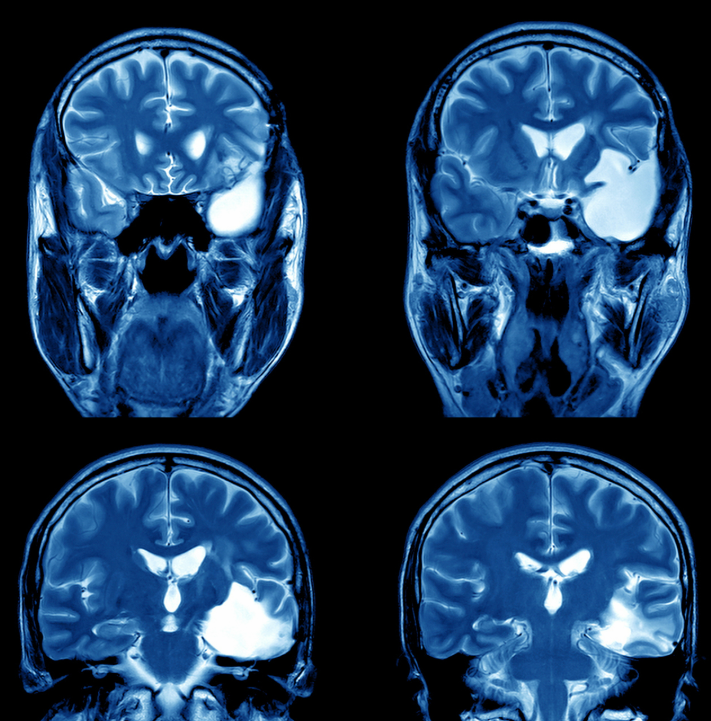

从医学检查角度看,轻微脑震荡患者的神经系统查体头部CT及磁共振成像MRI结果均无异常,说明脑实质未发生器质性病变这一特征与更严重的脑损伤如脑挫裂伤颅内血肿形成鲜明对比,后者常因脑组织损伤或出血导致长期后遗症治疗与预后方面,轻微脑震荡以对症支持治疗为主,包括充分休息避免剧烈;自主神经功能紊乱如出冷汗心跳加快易紧张等,可能与脑部神经调节失衡有关3 需警惕的特殊情况若症状持续加重或出现新发异常如剧烈头痛呕吐肢体无力言语障碍等,需立即就医,排除颅内出血或其他严重损伤儿童老年人或合并基础疾病者恢复可能较慢,需更密切观察总结轻微脑震荡本身预后。